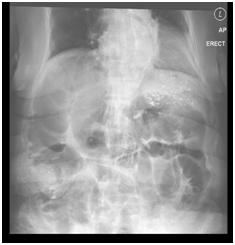

A computed tomography scan of Abdomen and Pelvis (CTAP) revealed distended small and large bowel loops, more so the colon, most significantly at the ileo-cecal junction. Pneumatosis of the cecum and terminal ileum was detected. There was mixed density pattern material in the stomach, terminal-ileum and cecal junction, suggestive of food material, which is not surprising in this case as this was an emergency CT scan. No pneumoperitoneum, free fluid or collection was detected. There was herniation of the small bowel into the mesentery. The celiac artery and superior mesenteric artery were patent, no occlusion or thrombosis was seen. There was also no cut off point suggestive of intestinal obstruction due to adhesion of tumor recurrence (Figure 2).

Figure 2 CT abdomen-Pelvis with contrast showing distended bowel and presence of bezoar.

The impression at that point of time was ischemic bowel secondary to intestinal obstruction due to small bowel herniation versus non-occlusive mesenteric ischemia. The patient then underwent an emergency exploratory laparotomy, completion colectomy with end ileostomy and on table endoscopy immediately. Intra-operatively, there was finding of a gangrenous cecum and ascending bowel with ischemic transverse colon (Figure 3), omentum adhered to pelvis and left iliac fossa due to adhesions from previous surgery. There was also internal herniation of small bowel via mesenteric window. In general, the small bowels were healthy, other than mildly dilated and having moderate adhesions of small bowel. Ischemic bowels with ulcerations were seen in the colon specimen. An on-table colonoscopy of rectal stump, which was done to determine the viability of the large bowel, showed healthy mucosa. Retrospectively, the histology of the excised specimen revealed mucosal necrosis, which was consistent with ischemia, as well as viable muscular is propria at bowel resection margins.

Figure 3CT abdomen-Pelvis with contrast showing distended bowel and presence of bezoar.